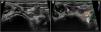

A-C) Ecografía Doppler vascular que muestra seudoaneurisma en proyección longitudinal (20mm) y transversal (14×10mm) con flujo turbulento en su interior. D-F) Imágenes de la angio-TAC que confirman el seudoaneurisma dependiente de la arteria ilíaca interna izquierda con permeabilidad de los vasos distales.